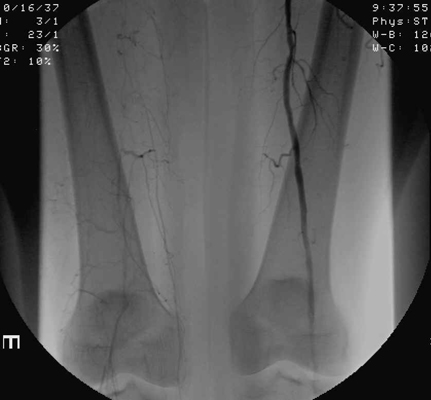

The images shown demonstrate increased collateral vessels and an occluded SFA on the

right. These images are critical to help the surgeon decide between possible

treatment options (bypass, angioplasty, or amputation). Clinical exam and imaging

aid in the decision as to what level to select when amputation is deemed necessary.